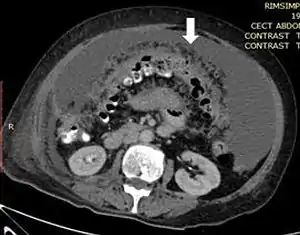

| Axial abdominal computed tomography featuring omental caking due to peritoneal carcinomatosis | |

Omental cake is a radiologic sign indicative of an abnormally thickened greater omentum.[1] It refers to infiltration of the normal omental structure by other types of soft-tissue or chronic inflammation resulting in a thickened, or cake-like appearance.[2]

Due to the variety of symptoms experienced by patients with omental caking,[5] omental cakes are most frequently discovered on abdominal computed tomography (CT) or ultrasound. Plain film radiography (X-ray) is not a suggested modality for investigating the spread of cancerous cells in the abdomen due to the poor spatial resolution amongst soft-tissue densities. Contrast resolution obtained through CT allows radiologists to investigate omental caking for morphology, intraperitoneal fluid, and regional lymphadenopathy assists in proper diagnosis so clinicians, surgeons, and oncologists can plan the appropriate course of treatment.[8]